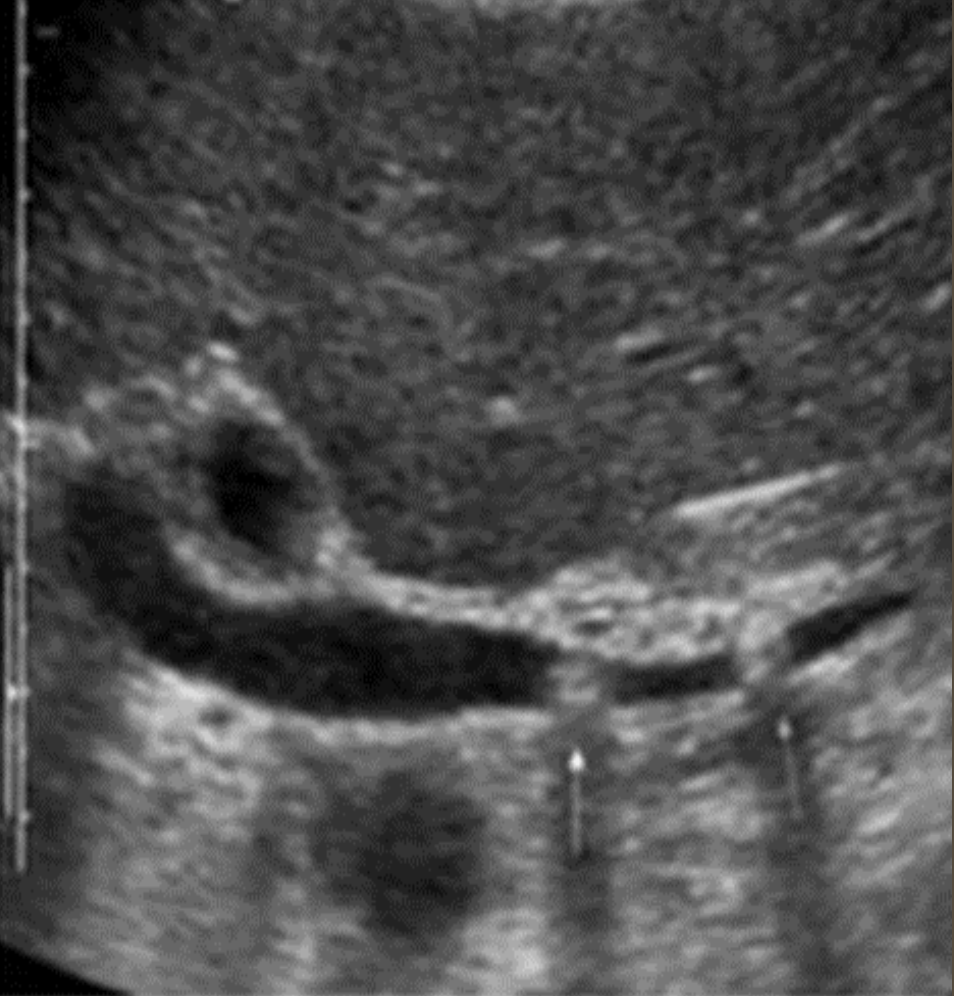

Aortic Dissection → intimal wall tears and allows blood flow between layers

2D US presentation: thin echogenic linear membrane fluttering in lumen creating a true and false lumen

color doppler: fill in both channels → pw shows regular flow in true and weak/no flow in false; asymmetrical kidney perfusion

DDX: AAA (focal dilation, no intimal flap)